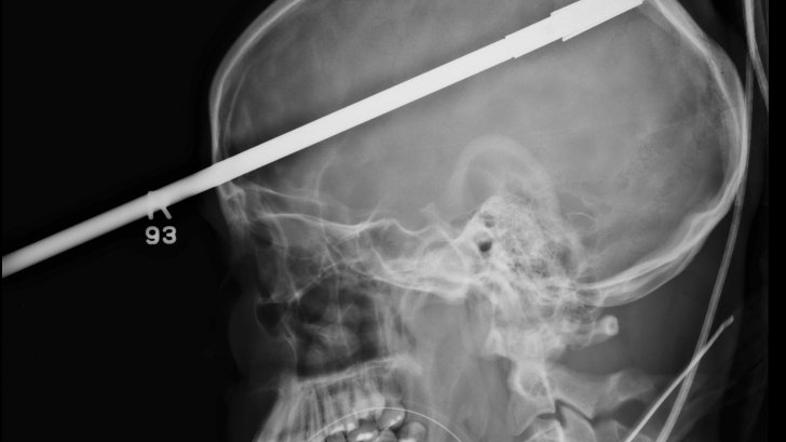

Glavo mu je preluknjala harpuna

Šestnajstletnik čudežno preživel strel v glavo s harpuno. Posledic ne bo imel.

Harpuna je Yasserja zadela tik nad desnim očesom in na drugi strani glave pogledala ven. Čudežno ni zadela nobenega od pomembnejših možganskih centrov, zato Yasser ne bo čutil nobenih posledic.